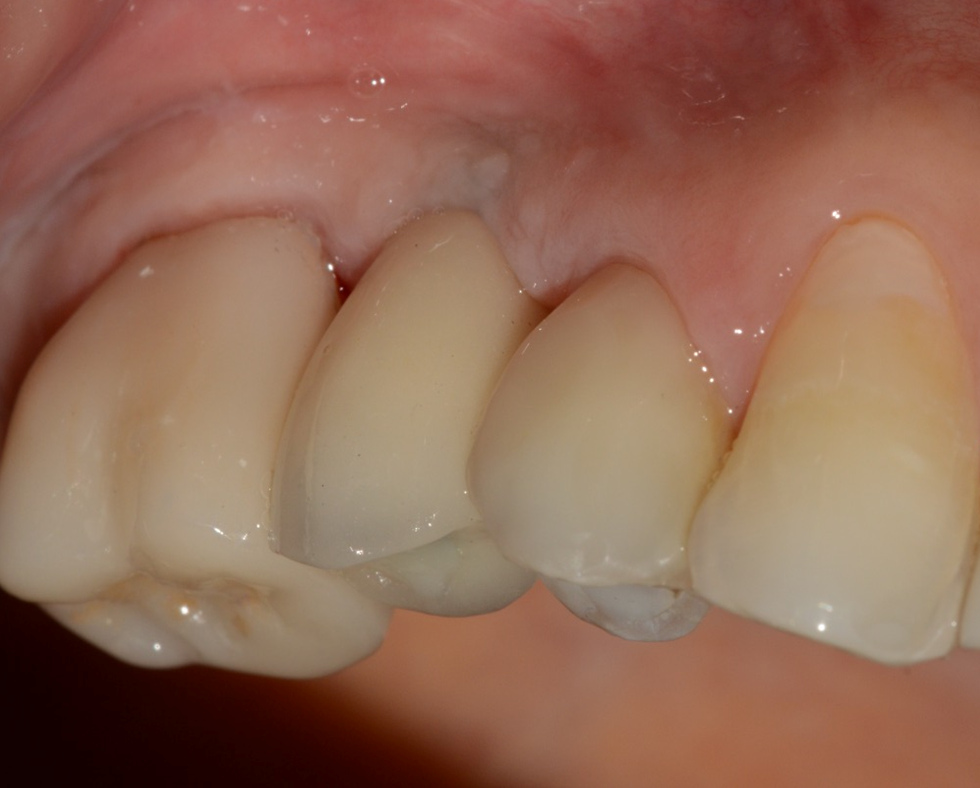

Aguardado o tempo, foi realizada a reabertura do implante com incisão deslocada para a palatal, deixando mais mucosa ceratinizada por vestibular (Figura 12). Foi instalado um Pilar Ideale (Figura 13) e confeccionado um provisório parafusado sobre ele. As suturas acomodaram a mucosa sobre o provisório, conformando-a ao perfil de emergência desejado (Figura 14).

Após 21 dias, a mucosa se apresentava saudável e com um perfil de emergência adequado para a confecção da coroa protética definitiva sobre implante (Figura 15). Foram realizados os procedimentos de moldagem com personalização do transferente para a cópia fiel do perfil de emergência, e uma coroa metalocerâmica foi instalada sobre o Pilar Ideale e a reabilitação foi finalizada (Figura 16).